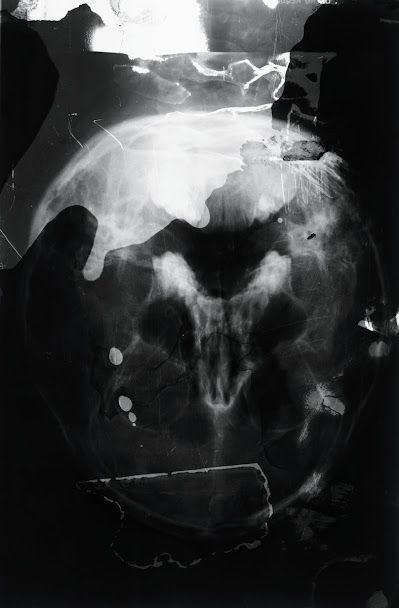

AU DELA DES CORPS PERDUS

Pendant le COVID , aucun matériel pour travailler n'était disponible chez moi.

J'ai alors utilisé mes propres radiographies, des produits de ménage et des instruments du quotidien.

Je savais que le matériau de départ, les radiographies, allaient disparaitre, remplacées par des c.d.

Puis j'ai réussi à me procurer d'autres radiographies et mon dialogue avec la trace

et la disparition des corps a pu se rétablir.